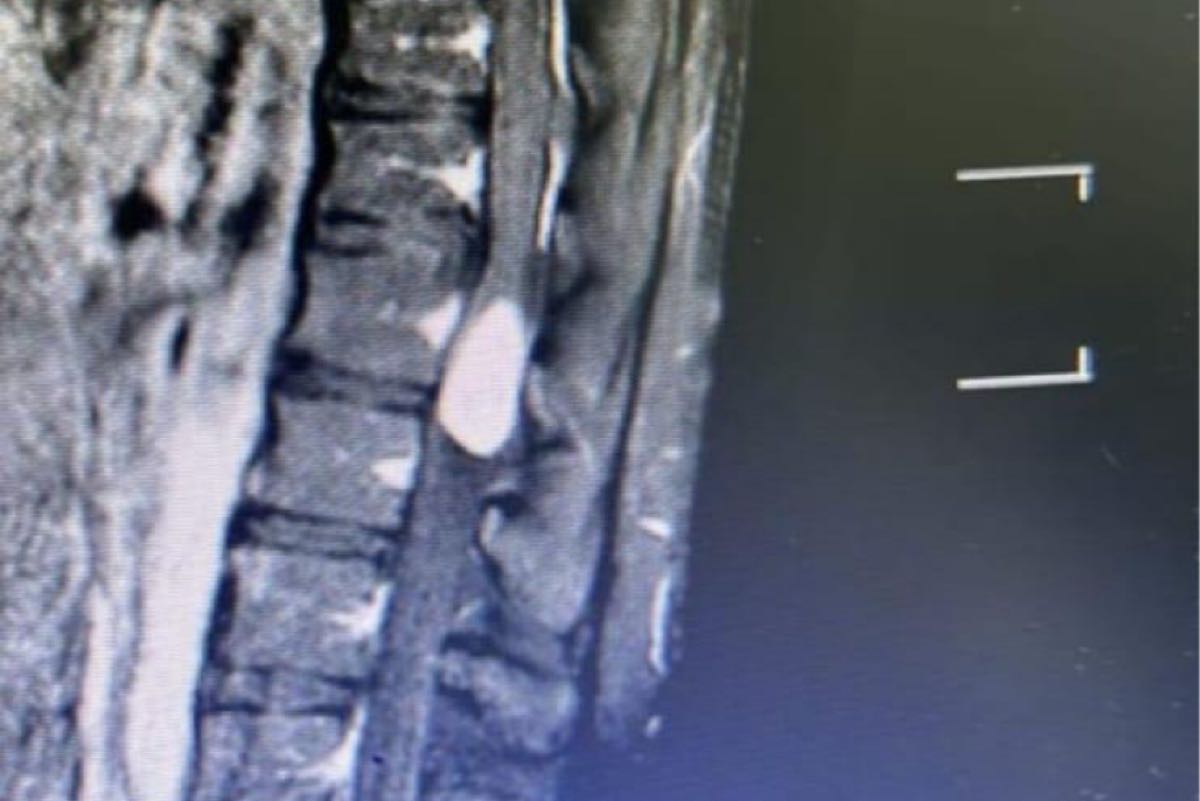

القطيف.. عملية دقيقة تنجح في استئصال ورم داخل الحبل الشوكي لشاب عشريني

تمكن فريق طبي متخصص من قسم جراحة المخ والأعصاب والعمود الفقري في شبكة القطيف الصحية، من إجراء عملية جراحية دقيقة وناجحة لاستئصال ورم ضمن الحبل الشوكي لشاب في العقد الثاني من العمر.

وأوضح أن الورم الذي تم استئصاله كان يسبب ضغطاً شديداً على الحبل الشوكي، مما يؤثر على حركة الشاب وقدرته على القيام بأنشطته اليومية بشكل طبيعي،